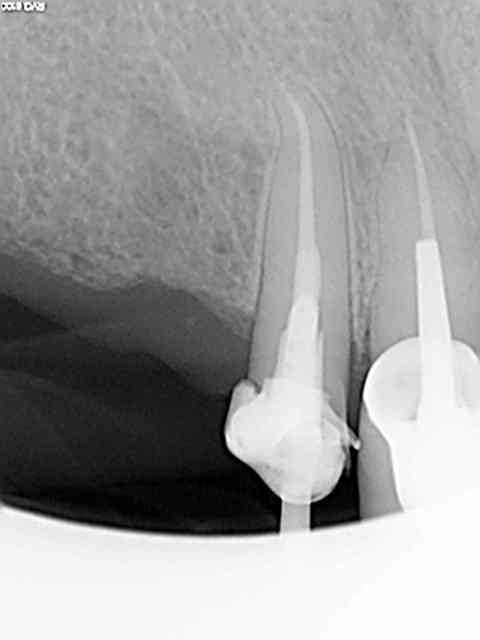

05/11/2013 à 13h04

Exemple sur cette 12 tout à l'heure, 1h 30 de rdv terminé en 1h et encore j'ai un peu "tâtonné" pour trouver la pulpe. Toujours pas de cathétérisme manuel of course sinon j'y serais encore.)))))